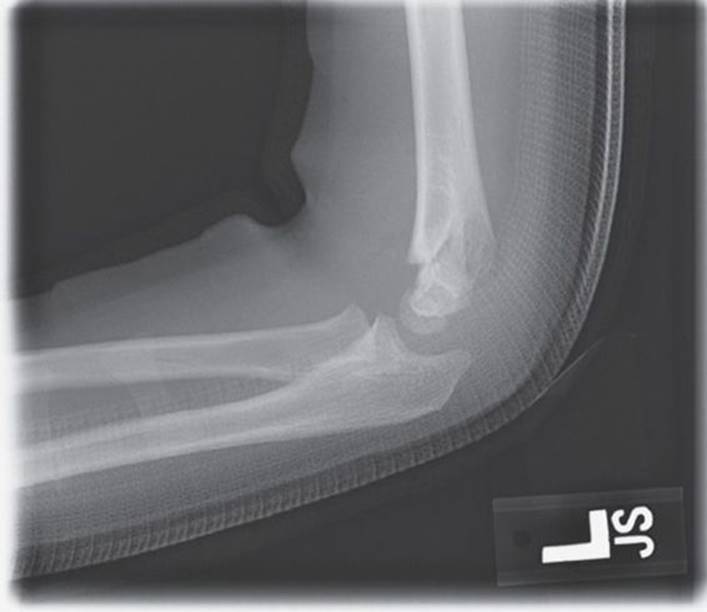

Pediatric elbow dislocations occur infrequently, as most forces that would result in dislocations in adults usually cause fractures in children (Fig. 30-7). When elbow dislocations do occur, they are usually the result of a fall onto the slightly flexed, outstretched arm in an adolescent. Most dislocations are posterior.

FIGURE 30-7. Posterior elbow dislocation with avulsion of the medial epicondyle.

Associated fractures are the rule and most commonly involve fracture of the medial epicondyle, coronoid process, radial head, or olecranon. Significant damage to the surrounding soft tissues also occurs, with damage to the nerves more commonly than brachial artery injury. Recovery of function of the ulnar nerve can be expected, but the prognosis is less optimistic with median nerve injury. Vascular compromise complicates up to 7% of pediatric elbow dislocations.18

Most dislocations can be reduced after providing adequate analgesia and muscle relaxation. The elbow should be flexed to 60 to 70 degrees and the forearm placed in supination. The proximal humerus is then stabilized by an assistant while longitudinal traction is applied at the wrist. Upon successful reduction, the elbow should be gently flexed and immobilized and the neurovascular status of the arm reappraised. Obtain a postreduction radiograph with attention to verifying the location of the medial epicondyle as extra-articular.